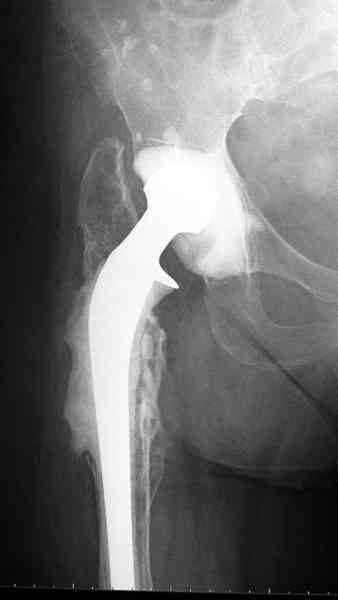

Приглашенный хирург установил ревизионный вариант бедренного компонента без замены ацетабулярного компонента, что осложнилось нагноением и свищами на уровне сустава и средней трети бедра. После двухгодичного безуспешного лечения перевязками и антибиотиками больная обратилась к нам на консультацию.

Для спейсера в бедро использовал старый длинный бедренний компонент меньшего диаметра, облепленный со всех сторон цементом с антибиотиком.

Наглухо ушитая рана с дренажом зажила первично, после чего с больной потерял контакт, и только недавно, через 8 лет я осмотрел её. Она без проблем нагружает на конечность и передвигается с помощью трости. От окончательной операции по реконструкции отказывается, довольная результатом.

Имеются литературные данные, когда спейсер держали не более 6 месяцев, но этот случай бьет все рекорды, может быть для наших людей, обременных финансовыми трудностями, нужна другая шкала оценки сроков нахождения спейсеров.

№3-6 снимки с осложнением

и последние снимки.